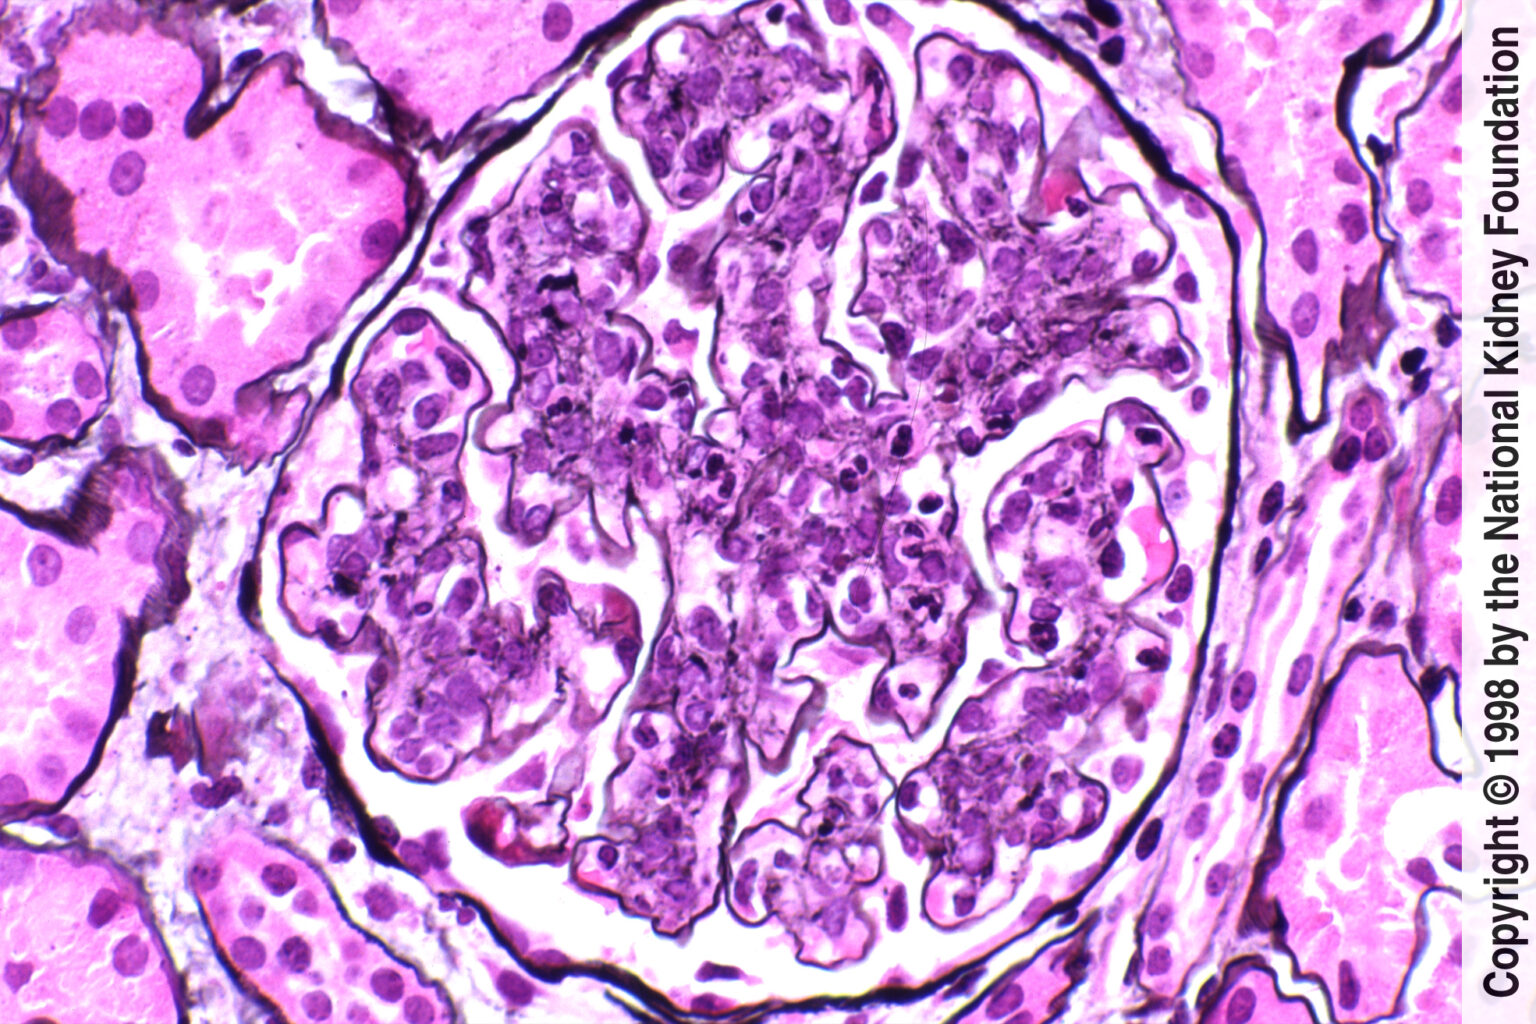

Program je zasnovan kot poglobljen in praktično usmerjen pregled: od prepoznave na primarni ravni in pravilne napotitve v nefrološko obravnavo do razumevanja patofiziologije, diagnostike in aktualnih terapevtskih pristopov. Obravnavali bomo ključne glomerulne bolezni (npr. IgA glomerulonefritis, podocitopatije, sistemske vaskulitise, s komplementom povezane glomerulne bolezni ipd.) ter obravnavo v posebnih stanjih (nosečnost, dializa, presaditev ledvice). Predstavili bomo tudi sistematično zbrane izkušnje UKC Ljubljana pri posameznih boleznih v obdobju 10 let in več.

Šola glomerulnih bolezni je namenjena specialistom in specializantom vseh specialnosti, ki v klinični praksi obravnavajo bolnike z glomerulno boleznijo ali s sistemsko avtoimunsko boleznijo z ledvično prizadetostjo – prvenstveno nefrologom, revmatologom in družinskim zdravnikom, pa tudi vsem zdravnikom, ki želijo pridobiti ali nadgraditi znanje o glomerulnih boleznih ter se seznaniti s sodobnim pristopom k bolniku z glomerulonefritisom.